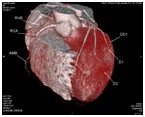

心脏大血管CT成像

冠状动脉CT成像